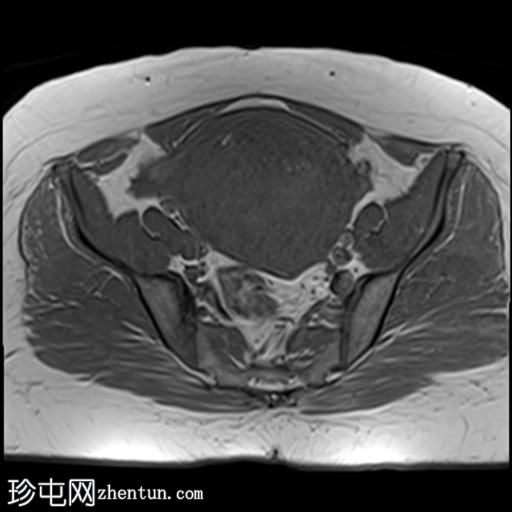

轴位

T2加权像

子宫增大,子宫内膜-肌层交界区弥漫性增厚,T1加权像呈中等信号,最高达45 mm;T2加权像呈低信号,内含多个小的高T2信号灶,提示月经出血渗入异位子宫内膜组织,符合弥漫性子宫腺肌症的

影像

学表现。

卵巢可见多个小的单房囊肿,无分隔或实性成分,最可能是浆液性包涵囊肿。

MRI表现最符合弥漫性子宫腺肌症。